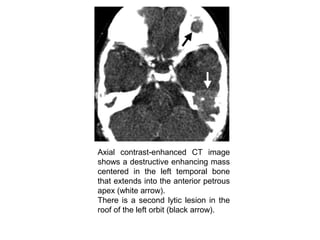

Axial contrast-enhanced CT image

shows a destructive enhancing mass

centered in the left temporal bone

that extends into the anterior petrous

apex (white arrow).

There is a second lytic lesion in the

roof of the left orbit (black arrow).